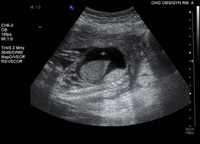

Transfusión intraperitoneal; se visualiza la punta de la aguja ecogénica en la cavidad de la ascitis

Ottawa Hospital; utilizado con el consentimiento de la paciente